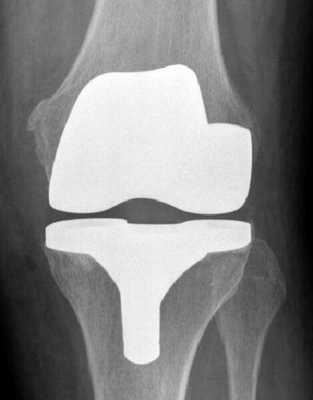

Рентген после операции. Протез стоит корректно.